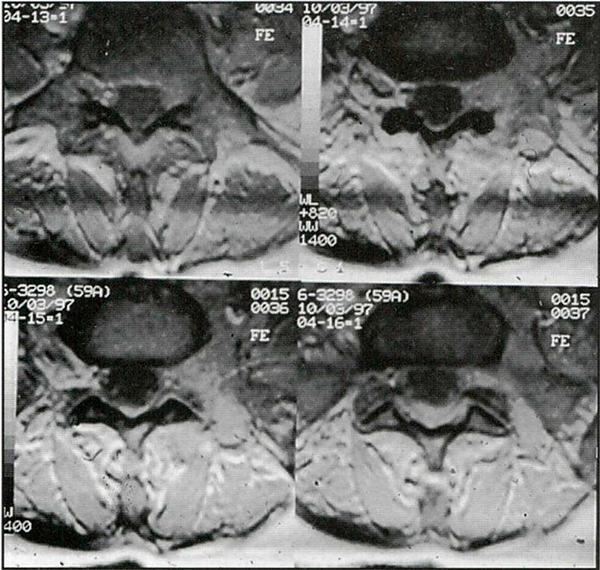

Caso 1: paciente de sexo femenino y 59 años de edad, con antecedentes de linfoma primario de piel, consultó por dolor radicular y paresia del miembro inferior izquierdo en el territorio L5. Las imágenes por resonancia magnética (IRM) de la columna lumbar mostraron a nivel foraminal y extraforaminal en L5-S1 un tejido blando hiperintenso con respecto al líquido cefalorraquídeo (LCR) que Infiltraba los tejidos vecinos y se introducía dentro del canal a través del foramen (Fig. 1). La paciente fue tratada con 16 mg/24 horas de dexametasona y antiinflamatorios no esteroideos 72 horas antes de ser llevada a cirugía para tomar biopsia y liberar la raíz nerviosa afectada.

Fig. 1. IRM axiales ponderadas en TI que muestran un tejido blando hiperintenso con respecto al LCR que ocupa las regiones foraminal y extraforaminal izquierdas

Caso 2: paciente de sexo femenino y 33 años de edad, sin antecedentes significativos, consultó por dolor radicular en el territorio L5 derecho de un año de evolución. Las IRM mostraron sólo signos de degeneración artrósica discal múltiple. La radiografia simple mostró una megapófisis transversa de L5 derecha que se articulaba con el sacro (Fig. 2). Se interpretó que ésta era la causa de sus síntomas y la paciente fue llevada a cirugía para resecar la megapófisis.

Fig. 2. Rx simple que muestra una megapófisis transversa de L5.

Flg. 5. Rx simple postoperatoria que muestra la falta de la megapófisis transversa de L5.

El dolor radicular desapareció en los casos 1 y 2 en el postoperatorio inmediato. La biopsia en el caso 1 fue informada como tejido inespecífico y en el caso 3 como ganglioneuroma. En el caso 2 la radiología postoperatoria confirmó la resección de la megatransversa (Fig. 5). El dolor postoperatorio respondió fácilmente a los analgésicos comunes. En los tres casos el alta se produjo a las 72 horas sin complicaciones.